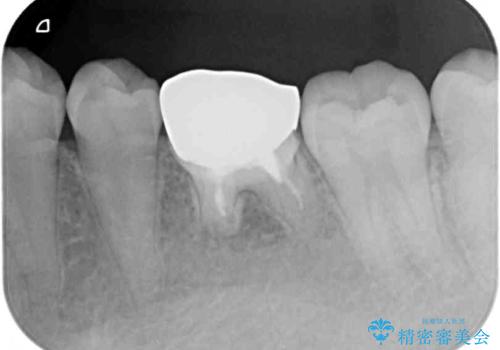

奥の銀歯も気になっていたため、矯正治療後にセラミッククラウンにて補綴することとしました。

1年半程度の期間を見込んでいましたが、上下の真ん中の位置をできる限り合わせるための調整に少し時間がかかってしまいました。

咬み合わせが安定し、前歯の汚れも付きにくくなりました。